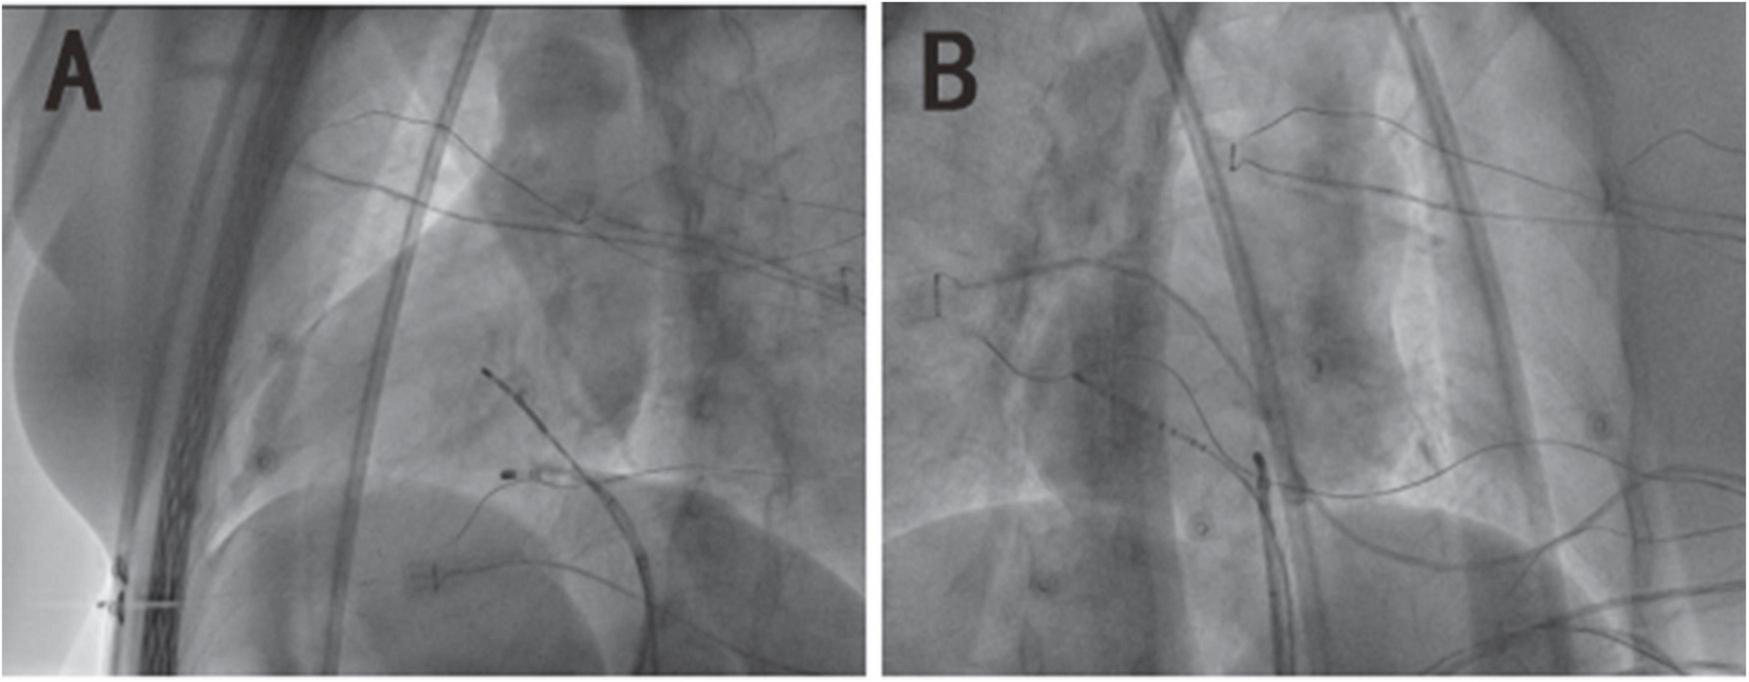

This procedure was performed under standard local anesthesia and guided by CARTO electroanatomical three-dimensional (3D) mapping system. A steerable Decapolar catheter (XTTM, Bard Electrophysiology, Lowell, MA, USA) and 4 polar catheters (AVAIL, Electrophysiology Cather, Biosense Webster, USA) were positioned in the coronary sinus (CS) through the right femoral vein. An 8.5-Fr long sheath (SL1, St. Jude Medical, MN, USA) was advanced into the right atrium through the right femoral vein, and a Thermocool Smart touch catheter was introduced to the region of His-bundle from SL1 (Figure 3). Supraventricular tachycardia was induced with the frequency of 180 beats per minute by ventricular S1S1, and A was reset by right ventricular apex entrainments and RS2 stimuli. The patient was diagnosed with dextrocardia with a posteroseptal tricuspid annulus accessory pathway by the intracardiac EGM (Figures 4A,B). After ablation at 43°C and 30W for 5 s, the accessory pathway was blocked and continued to ablate for 240 s. Retrograde Wenckebach conduction was stimulated by ventricular S1S1 for 400 ms, decreased conduction was stimulated by coronary sinus S1S1 stimulation, and Wenckebach conduction was found for 300 ms. No ventricular conduction with atria stimulated by S1S2 of 450/300 ms, indicating that the procedure was successful. Delta wave disappeared on intracardiac and surface EGM (Figure 4C).

FIGURE 3

The X-ray image of mirror dextrocardia in the left anterior oblique view of 45° and right-anterior oblique view of 35°. (A) The image of dextrocardia in the left anterior oblique is presented as a common heart in the regular right anterior oblique. (B) The image of dextrocardia in the right anterior oblique is presented as a common heart in the regular left anterior oblique.